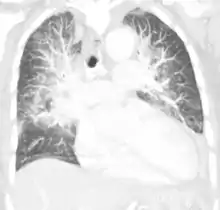

![]() Класична рентгенограма набряку легень Класична рентгенограма набряку легень | |